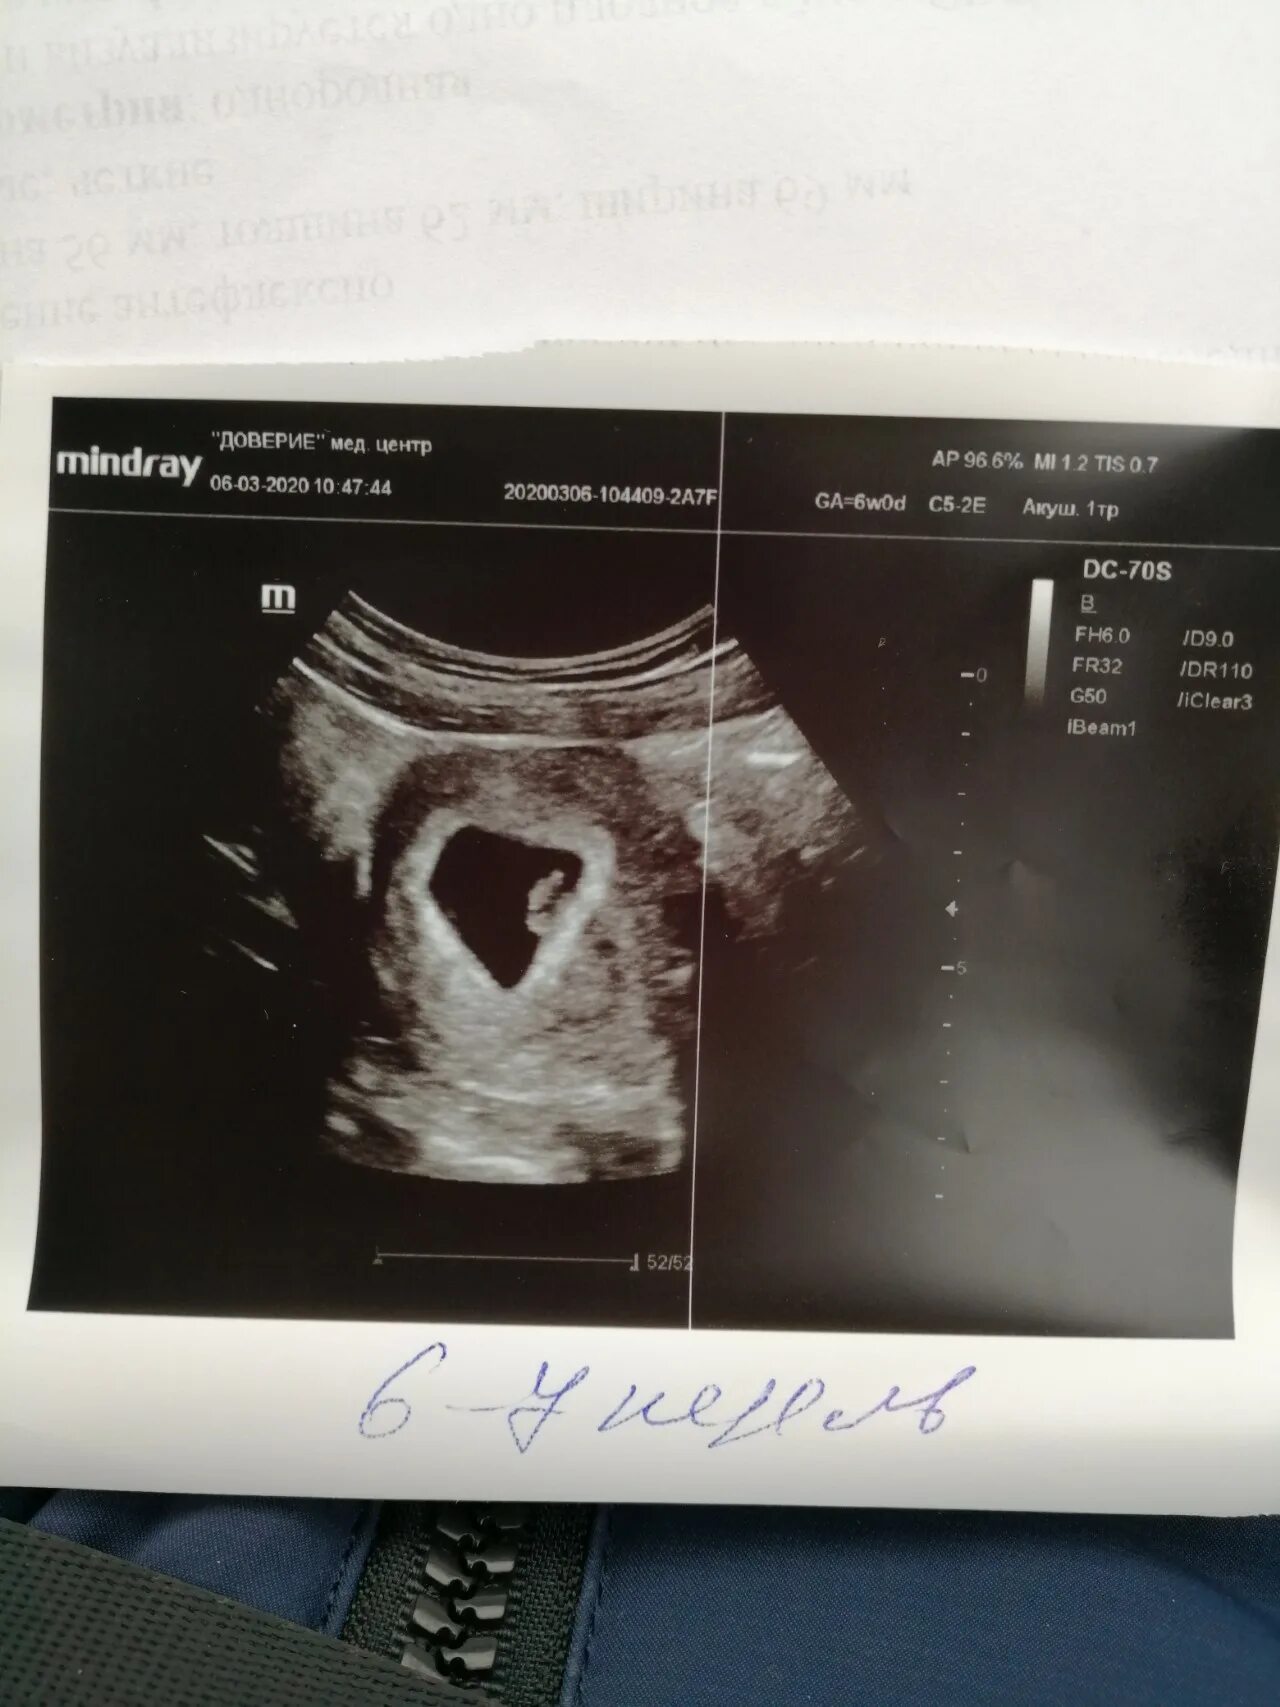

Коричневая мазня при беременности на ранних сроках беременности.7 недель после узи выделения. выделения при беременности 7 недель. выделения на 7 неделе беременности. выделения по неделям беременности.Коричневые выделения при беременности. коричневая мазня на 6 неделе. светло коричневые выделения на 6 неделе.7 недель беременности фото плода на узи. узи на 7-8 акушерской неделе беременности. фото эмбриона в 7 недель беременности фото узи. узи 7 недель беременности узи.Коричневая мазня на 7 неделе. коричневая мазня на 6 неделе беременности. коричневые выделения на 7 акушерской неделе.Коричневые выделения на 6 неделе беременности. выделения на 6 акушерской неделе. коричневые выделения 13 акушерская неделя беременности. 7 недель мажется коричневым.Выделения на 6 акушерской неделе. выделения на 6-7 неделе беременности норма. коричневые выделения на 6 неделе. коричневые выделения на 7 неделе.Узи беременности на ранних сроках. замершая беременность узи. беременность на узи до задержки. узи замершей беременности на ранних сроках.Узи на 7 акушерской неделе беременности. 7 неделя беременности акушерская узи узи. узи 7 недель беременности акушерская фото плода. плод на 7 неделе беременности узи.Эмбрион на 7 акушерской неделе. плод 7 недель беременности размер плода. эмбрион 6-7 недель как выглядит. размер ребенка в 7 недель.Признаки ретрохориальной гематомы при беременности 6-7 недель. узи беременности на ранних сроках.Беременность на ранних сроках. выкидыш по срокам беременности.Мазня на пятой акушерской неделе. коричневые выделения на 7 акушерской неделе. узи 7-8 недель беременности. беременность на ранних сроках 5 недель.Выделения срок 7 недельРетрохориальная гематома на 7 неделе беременности. узи 7 недель беременности гематома. гематома при беременности на ранних сроках. ретрохориальная гематома на узи.Размер ребенка на 7 неделе беременности. размер эмбриона на 7 неделе. плод 7 недель беременности размер плода.При беременности на ранних сроках. мазня при беременности до задержки. беременность выделения до задержки. выделения при беременности на ранних сроках после задержки.Плодное яйцо 6 недель по узи. плодное яйцо 7 недель узи. плодное яйцо 5 недель на узи беременность 6.Коричневатые выделения при беременности. слизистые коричневатые выделения при беременности. коричневатые выделения на ранних сроках беременности. темные коричневые выделения.Выделения срок 7 недельВыделения срок 7 недельЗаключение узи 7 недель беременности. 6 недель беременности по узи. узи беременности 4-6 недель. эмбриональный срок 5 недель узи.Выделения срок 7 недельКоричневые выделениепри беременности. мажущие коричневые выделения. светло коричневая мазня.Коричневатые выделения. светло коричневые выделения. светло желтые выделения.Узи на 2-4 недели беременности. узи беременности на ранних сроках. узи по беременности на ранних сроках.Светло бежевые выделения. желто бежевые выделения. светло розоватые выделения.Розово бежевые выделения. бледно розовые выделения на ранних сроках. бежево розовые выделения при беременности.Выкидыш на ранних сроках беременности. выкидыш на 6 неделе беременности. зародыш на 4 неделе выкидыш.Ведетентя при беременности. бледно коричневые выделения.Выделения на 5 неделе беременности. кровотечение на 5 неделе беременности. кровомазание на 6 неделе беременности. кровит на раннем сроке беременности.Выделения срок 7 недельКоричневатые выделения. выделения прибеременосьи. светло бежевые выделения.Выделения срок 7 недельИмплантационное кровотечение. мажущие кровянистые выделения. кровянистые розовые выделения.Светло коричневая мазня. светло бежевые выделения. небольшие розовые выделения.Темнокорияневве выделения. темно коричневые выделения. темные коричневые выделения.Узи 7 недель беременности гематома. гематома на узи при беременности. ретрохориальная гематома узи заключение.Выделения срок 7 недельРозово бежевые выделения. светло бежевые выделения. выделения розового цвета.